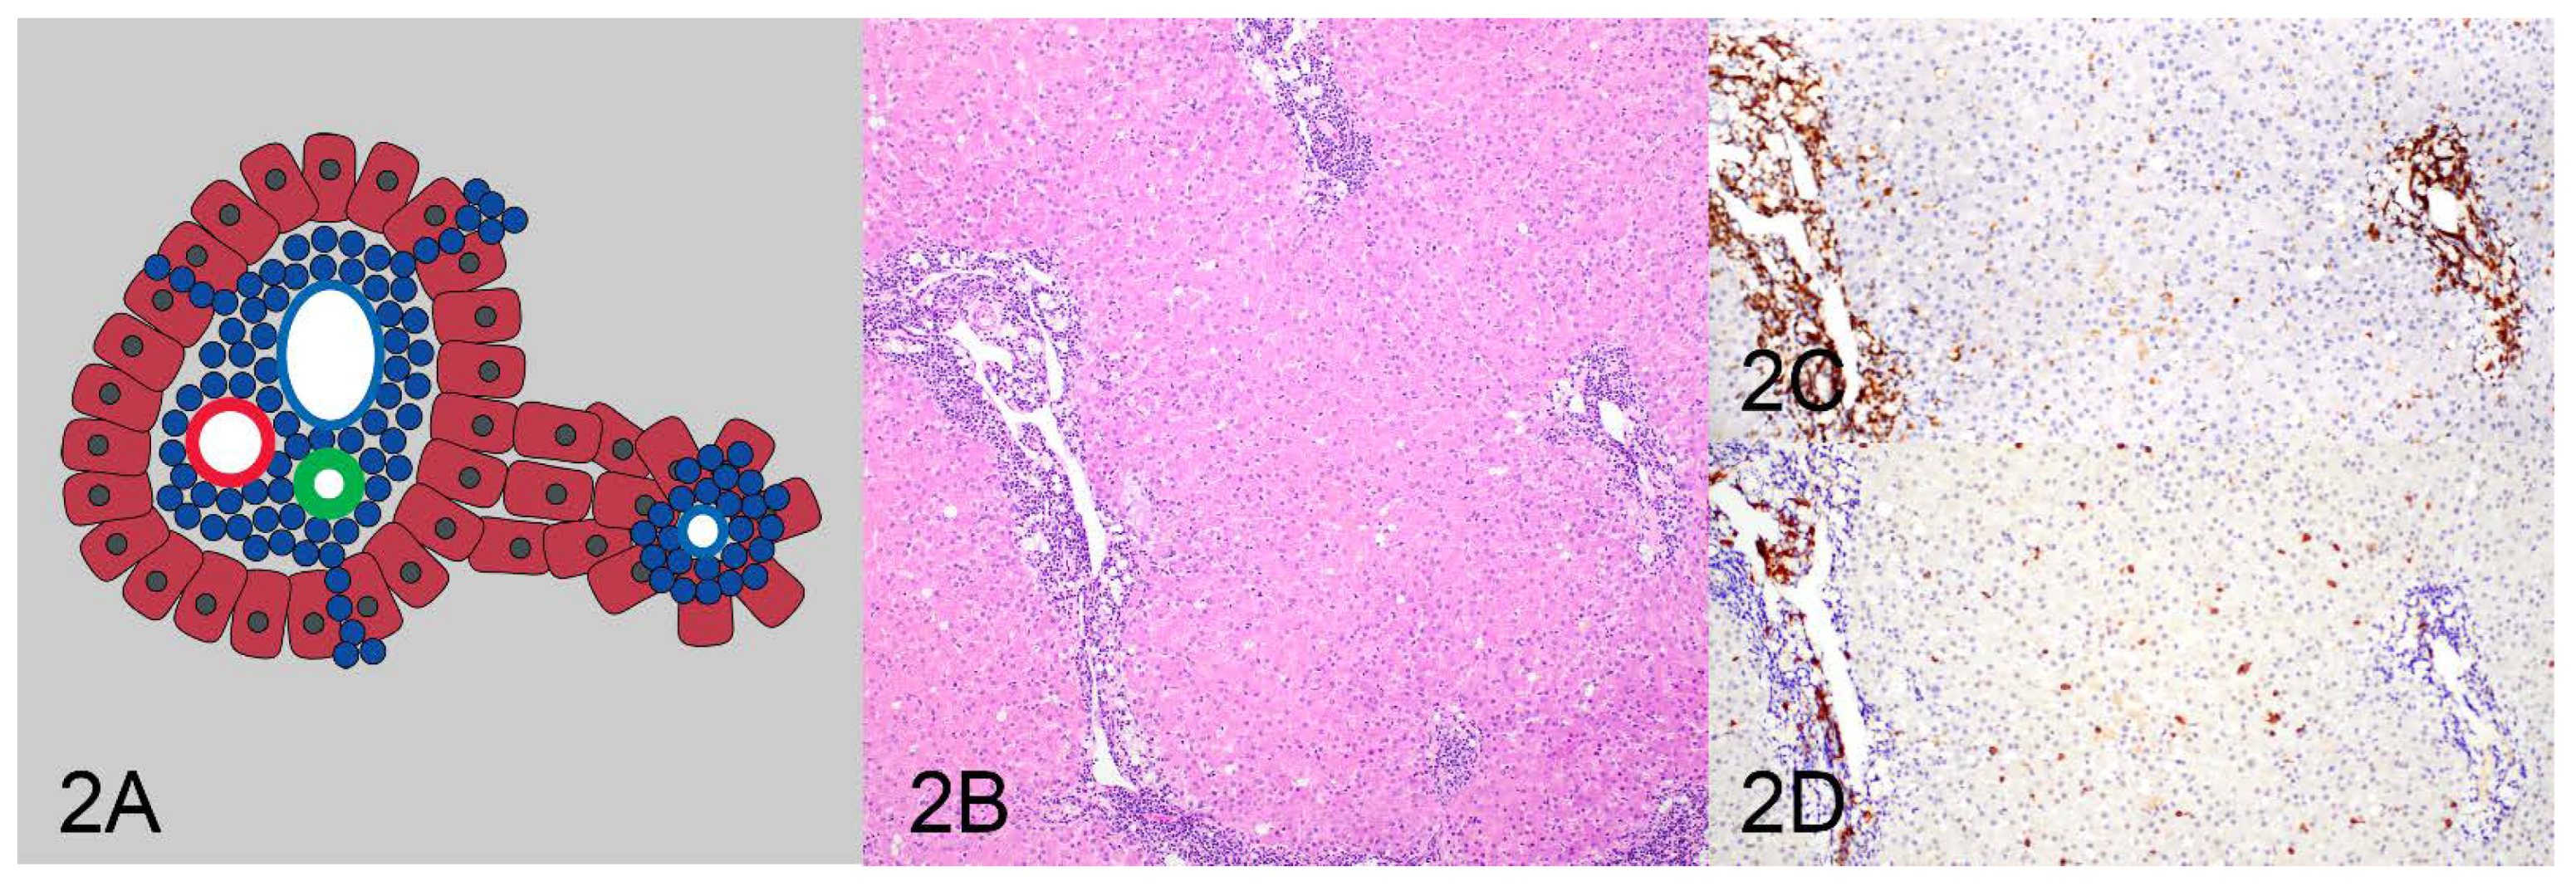

| Pattern 2: Periportal and centrilobular | 0 (0%) | 1 (100%) | 1 (100%) |